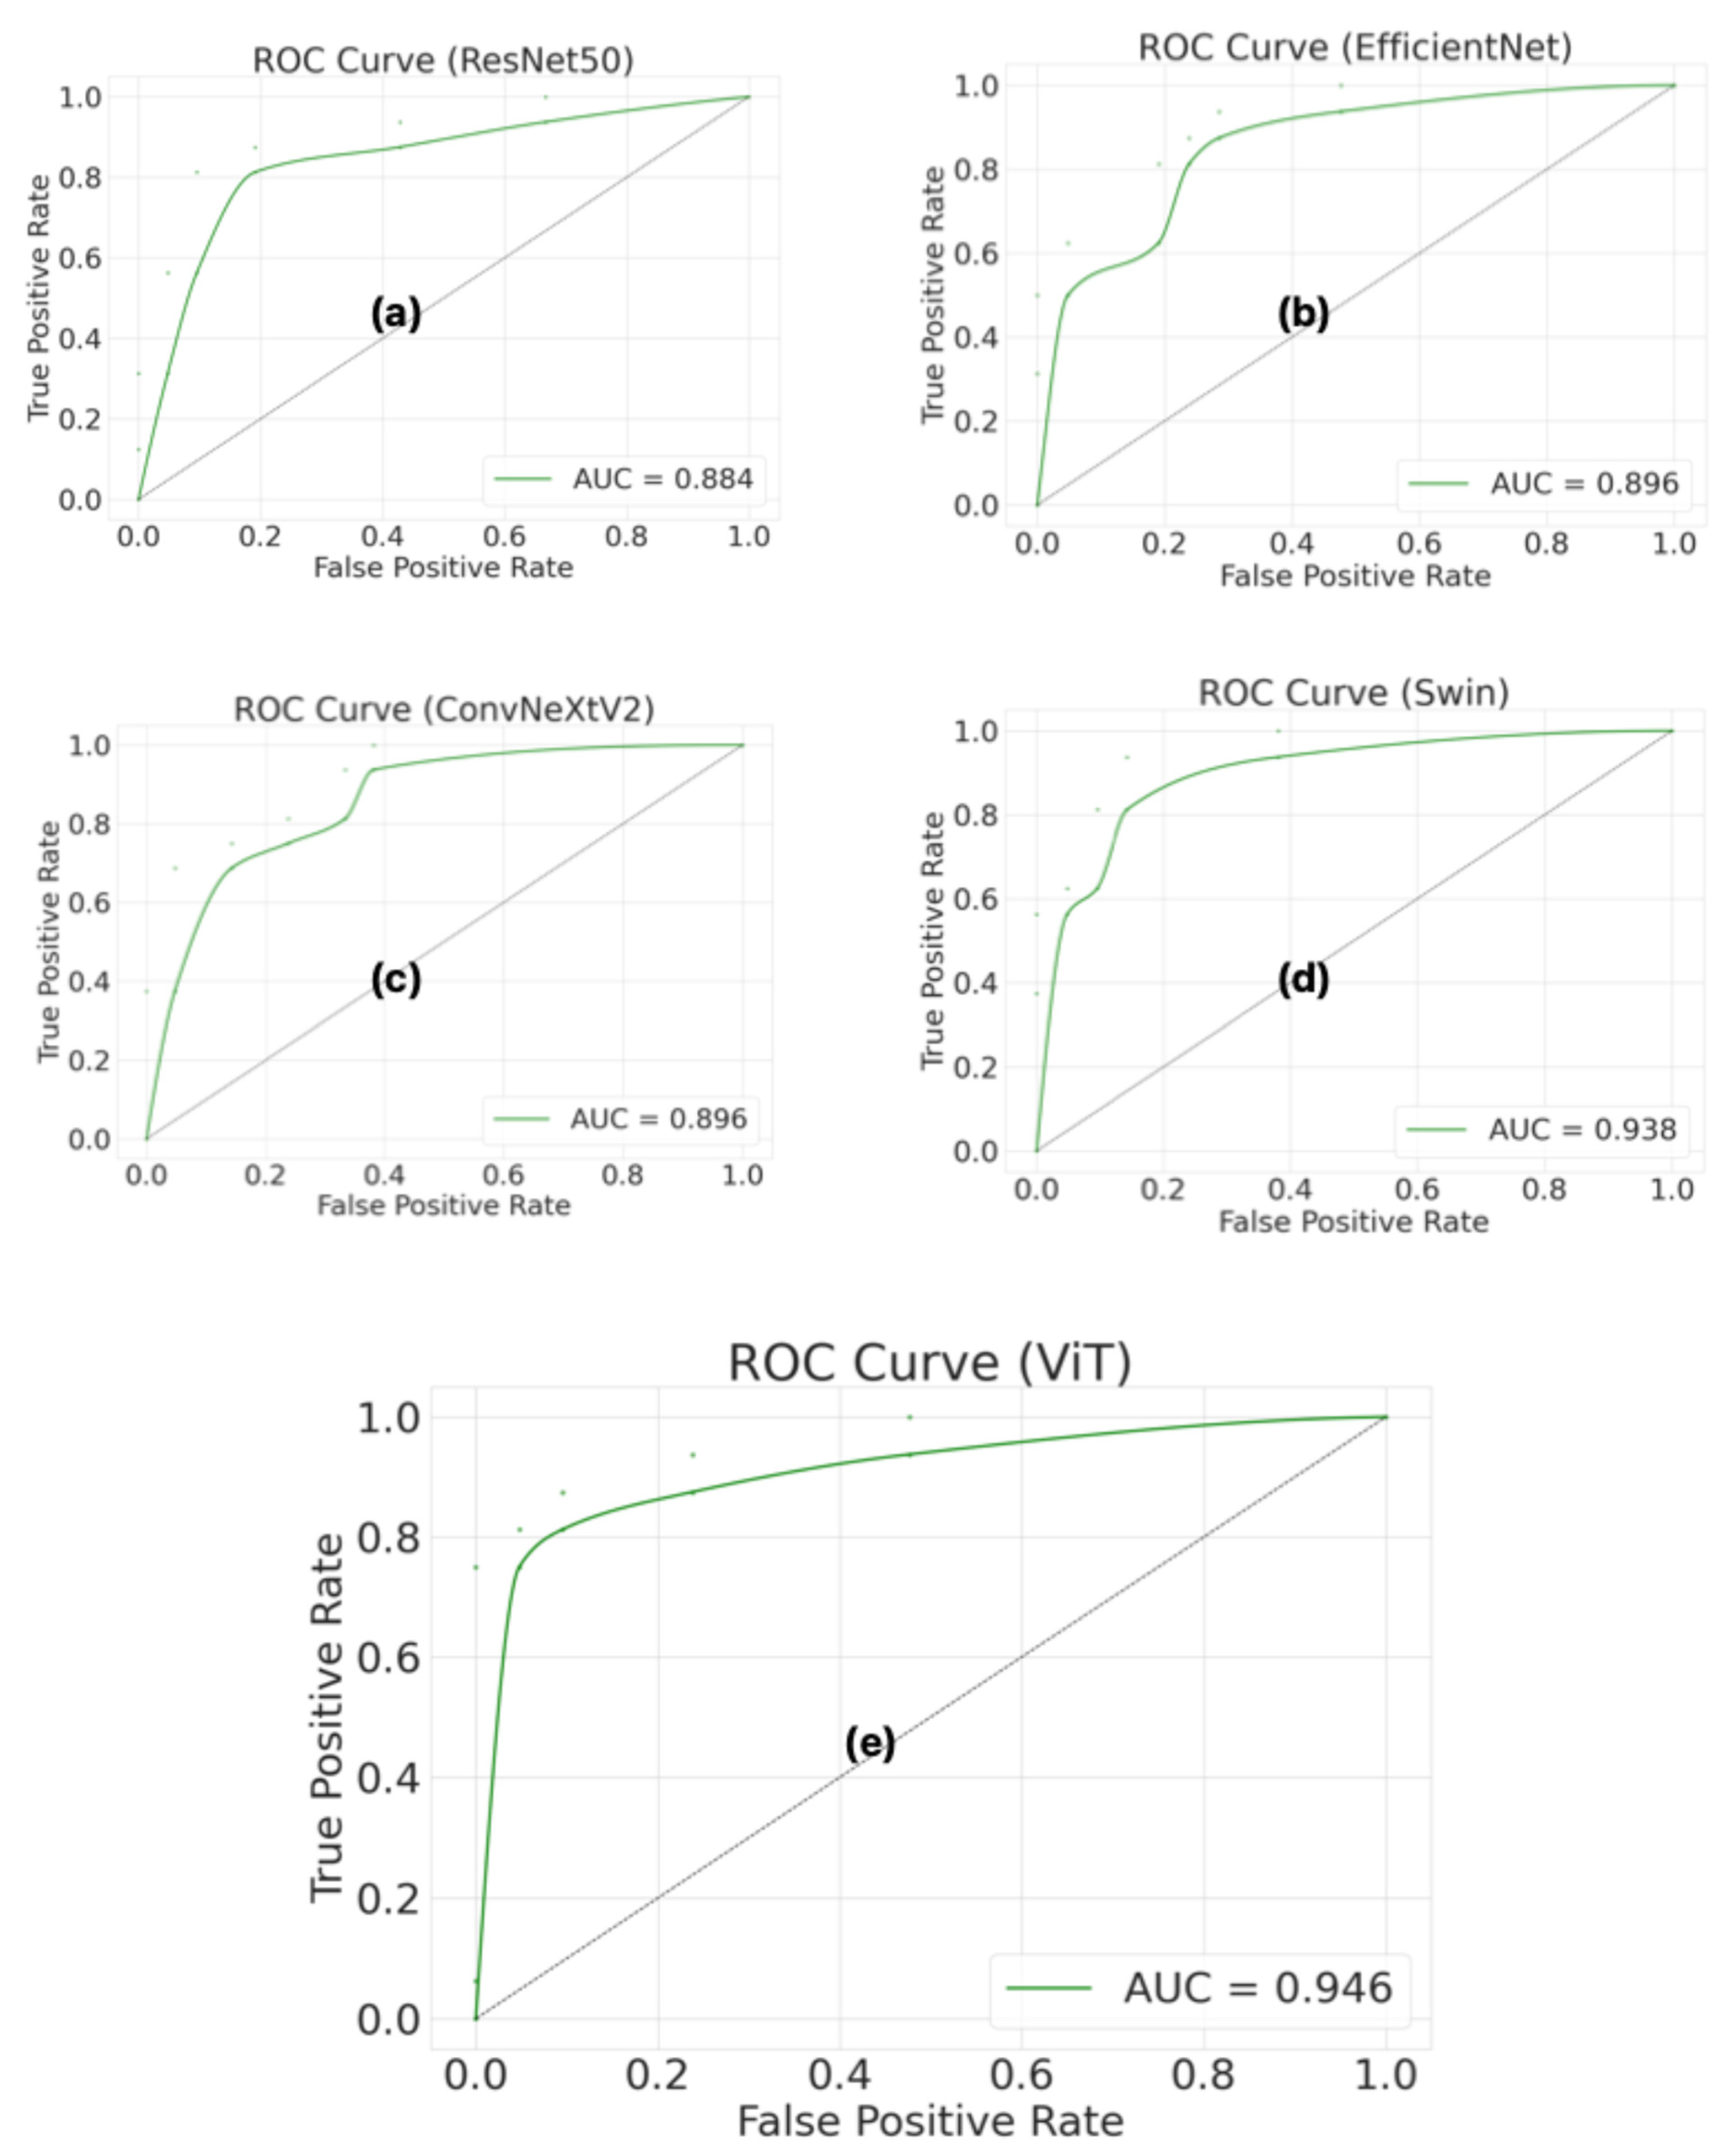

Figure 6 shows the receiver operating characteristic (ROC) curves and area under the curve (AUC) values for the ResNet50, EfficientNet, ConvNeXtV2, Swin, and ViT models, which were evaluated using a patient-level test set. The ROC curve and the AUC were used to evaluate the model’s ability to discriminate across different classification thresholds. The ViT model achieved the highest AUC value (0.946). The ViT model’s ROC curve is closest to the upper left corner, indicating that it performs better than other models in distinguishing between AP and normal pancreas classes. Furthermore, the high AUC value shows that the ViT model can provide high sensitivity and a low false positive rate at different thresholds. The Swin model indicated the closest performance to the ViT model, with an AUC of 0.938. The Swin model’s ROC curve is significantly distant from the diagonal line, indicating strong classification performance. The ConvNeXtV2 and EfficientNet models showed similar performance, with an approximately 0.896 AUC value for both. However, the ResNet50 model showed the lowest performance, with an AUC of 0.884. Additionally, the Swin model’s higher AUC value despite having the same confusion matrix results as ResNet50 indicates stronger overall classification performance. These findings confirm that the Swin model reveals more consistent and robust discrimination across all thresholds, not just at a single threshold.

In this study, CNN and transformer-based deep learning architectures were compared for the automatic classification of AP and normal pancreas from contrast-enhanced CT images, and the patient-level classification performance of the ViT architecture was evaluated in particular. The results revealed that the ViT model achieved higher Accuracy (89.19%), F1-score (86.67%), and area under the curve (AUC) with 0.946 than other CNN and transformer-based models. These results demonstrate that transformer-based architectures have a stronger representational capacity for distinguishing pathological changes in pancreatic CT images.

Overall, the enhanced performance of the transformer-based ViT architecture can be explained by its global contextual feature learning capability provided by its self-attention mechanism. Unlike CNN-based architectures, which generally focus on local feature extraction, transformer architectures can model long-range relationships between different regions within an image. This feature enables more accurate learning of complex pathological findings, such as inflammation, edema, and changes in tissue density in pancreatic tissue. ROC analysis results also support this, with the ViT model having the highest AUC value. This indicates that the model performs stronger discriminative performance across different threshold values. These results show that the ViT architecture is a powerful alternative for solving medical image classification problems and can be used as an effective decision support system for the automated diagnosis of critical diseases, such as acute pancreatitis.